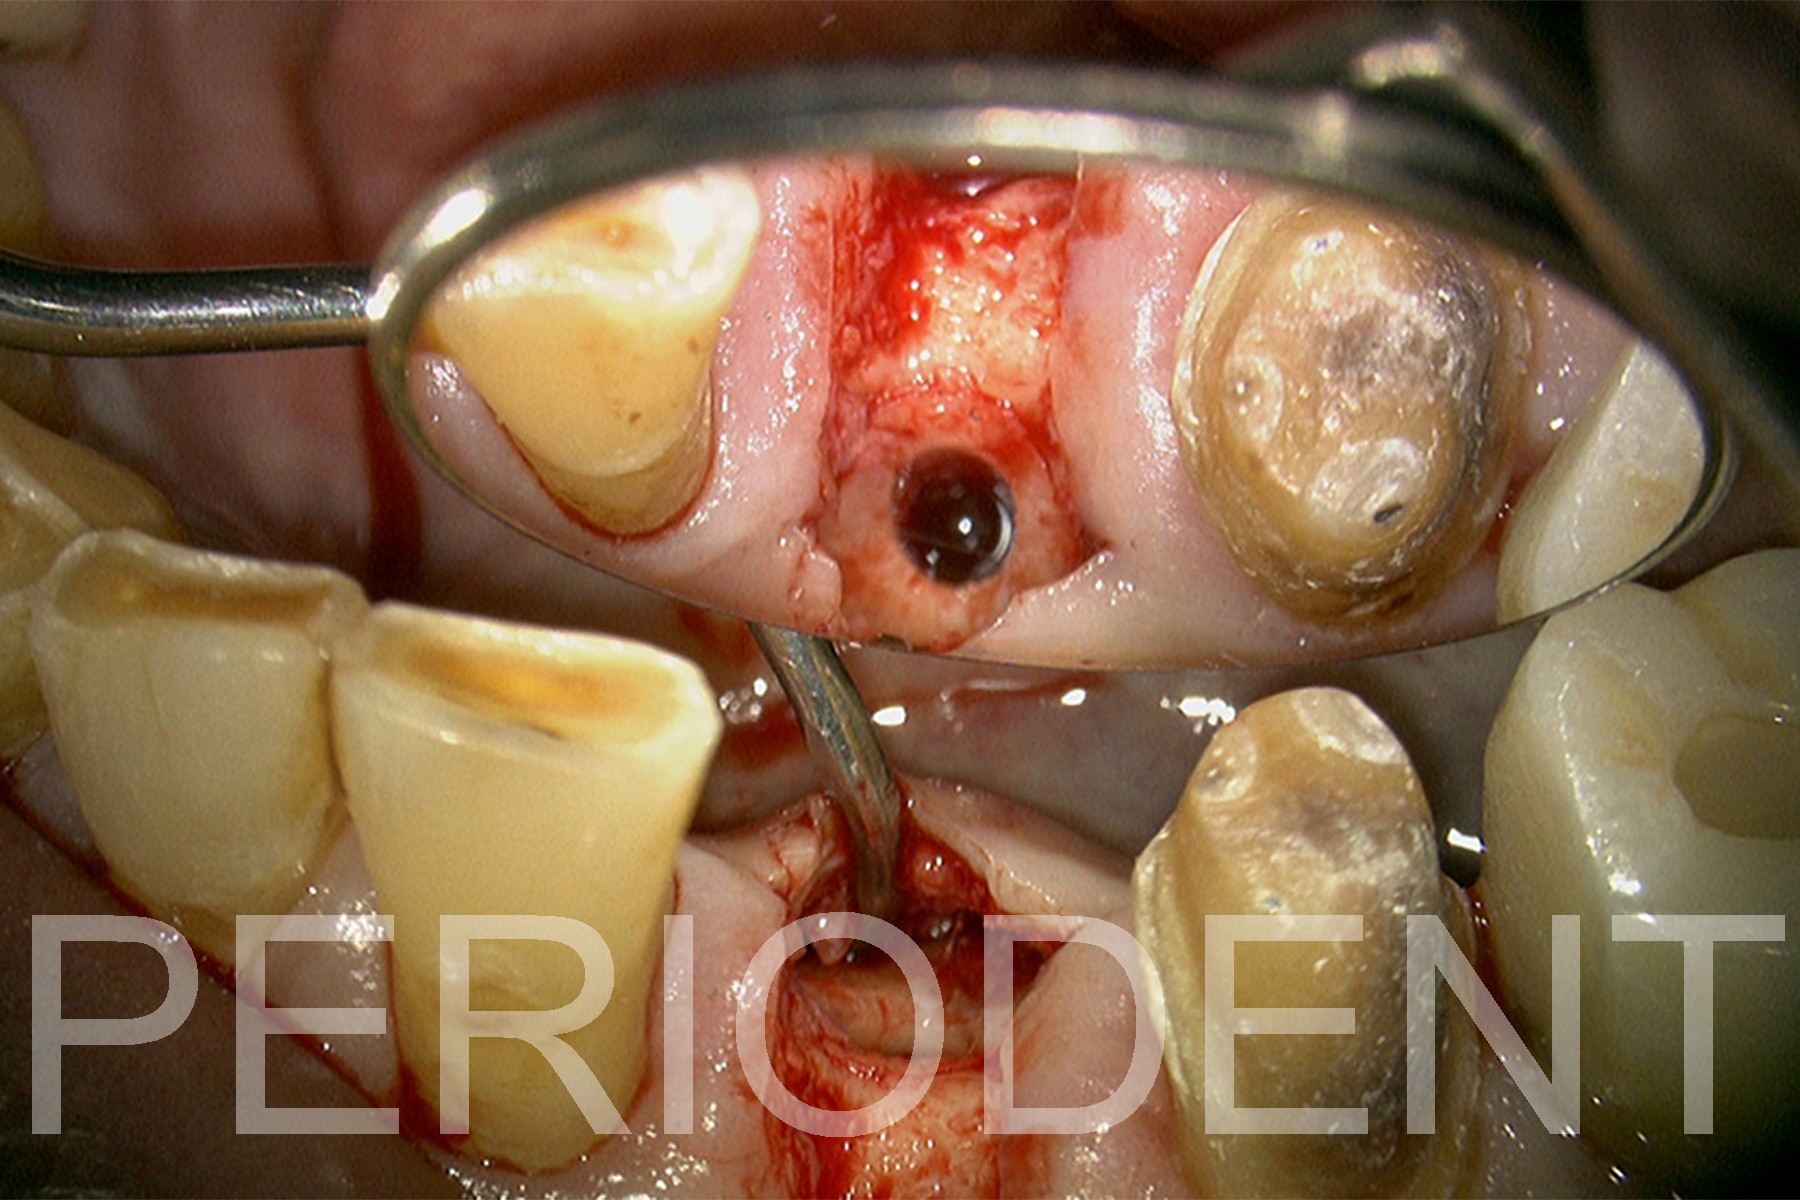

11. 一年後植牙時,去除過多的骨頭,以得適當的植牙台面高度

12. 植牙影片